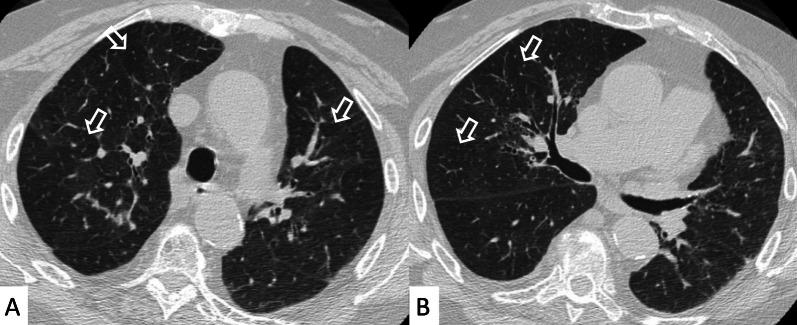

Connective tissue diseases (CTDs) include a spectrum of disorders that affect the connective tissue of the human body; they include autoimmune disorders characterized by immune-mediated chronic inflammation and the development of fibrosis. Lung involvement can be misdiagnosed, since pulmonary alterations preceded osteo-articular manifestations only in 20% of cases and they have no clear clinical findings in the early phases. All pulmonary structures may be interested: pulmonary interstitium, airways, pleura and respiratory muscles. Among these autoimmune disorders, rheumatoid arthritis (RA) is characterized by usual interstitial pneumonia (UIP), pulmonary nodules and airway disease with air-trapping, whereas non-specific interstitial pneumonia (NSIP), pulmonary hypertension and esophageal dilatation are frequently revealed in systemic sclerosis (SSc). NSIP and organizing pneumonia (OP) may be found in patients having polymyositis (PM) and dermatomyositis (DM); in some cases, perilobular consolidations and reverse halo-sign areas may be observed. Systemic lupus erythematosus (SLE) is characterized by serositis, acute lupus pneumonitis and alveolar hemorrhage. In the Sjögren syndrome (SS), the most frequent pattern encountered on HRCT images is represented by NSIP; UIP and lymphocytic interstitial pneumonia (LIP) are reported with a lower frequency. Finally, fibrotic NSIP may be the interstitial disease observed in patients having mixed connective tissue diseases (MCTD). This pictorial review therefore aims to provide clinical features and imaging findings associated with autoimmune CTDs, in order to help radiologists, pneumologists and rheumatologists in their diagnoses and management.

结缔组织病(CTDs)包括一系列影响人体结缔组织的疾病;它们包括以免疫介导的慢性炎症和纤维化发展为特征的自身免疫性疾病。肺部受累可能会被误诊,因为肺部改变仅在20%的病例中先于骨关节炎表现出现,且在早期阶段没有明确的临床发现。所有肺部结构都可能受累:肺间质、气道、胸膜和呼吸肌。在这些自身免疫性疾病中,类风湿关节炎(RA)的特征是普通型间质性肺炎(UIP)、肺结节和伴有空气潴留的气道疾病,而系统性硬化症(SSc)常表现为非特异性间质性肺炎(NSIP)、肺动脉高压和食管扩张。NSIP和机化性肺炎(OP)可见于多发性肌炎(PM)和皮肌炎(DM)患者;在某些情况下,可观察到小叶周围实变和反晕征区域。系统性红斑狼疮(SLE)的特征是浆膜炎、急性狼疮性肺炎和肺泡出血。在干燥综合征(SS)中,HRCT图像上最常见的表现是NSIP;UIP和淋巴细胞间质性肺炎(LIP)的报道频率较低。最后,纤维化NSIP可能是混合性结缔组织病(MCTD)患者中观察到的间质性疾病。因此,本图像综述旨在提供与自身免疫性CTDs相关的临床特征和影像学表现,以帮助放射科医生、呼吸科医生和风湿病科医生进行诊断和管理。